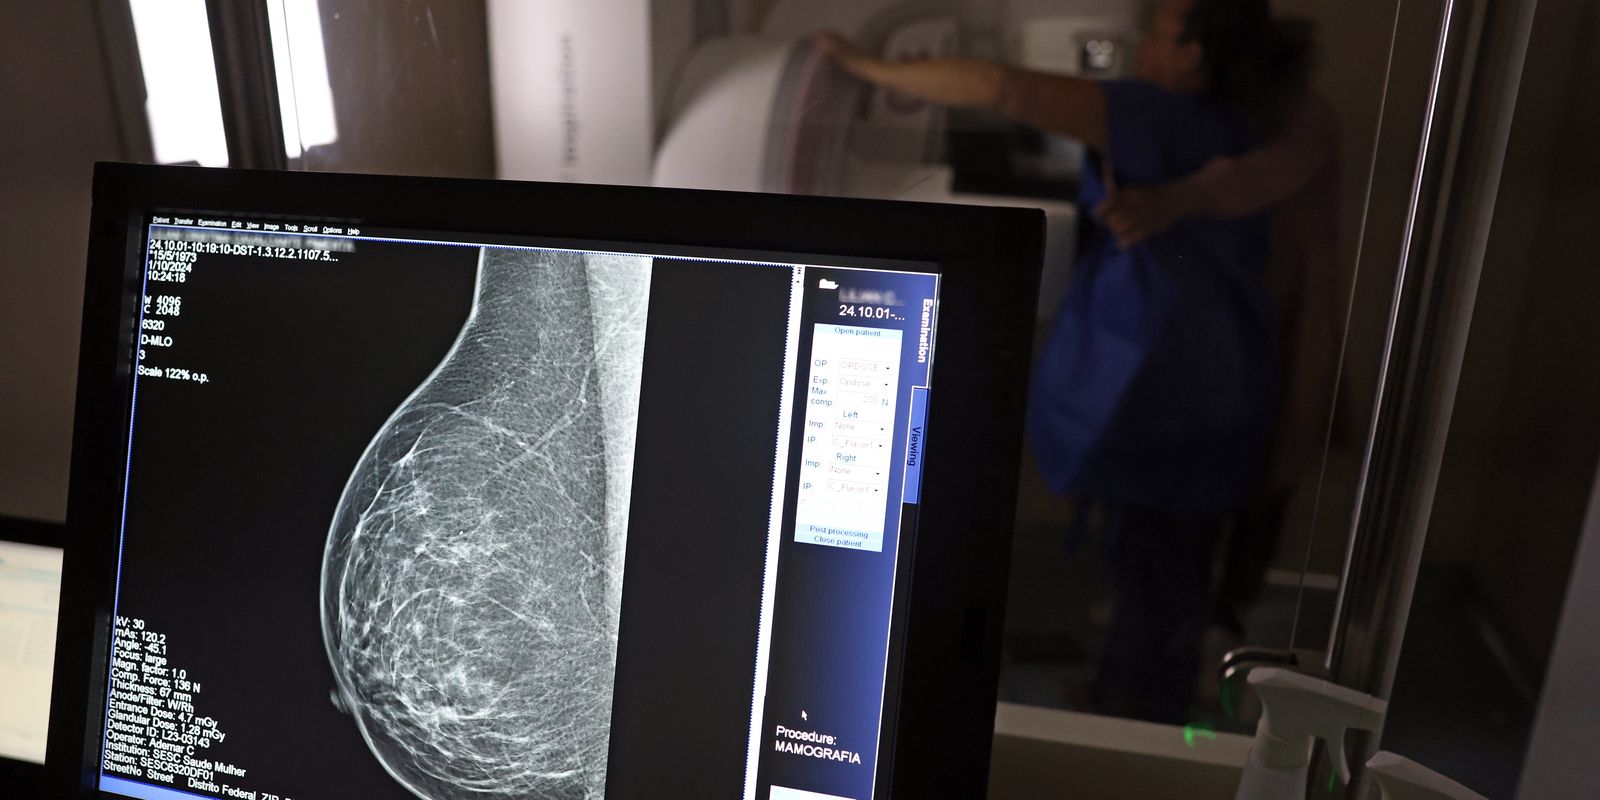

In Pink October, the National Cancer Institute (Inca) estimated 73,610 new cases this year in the country. It is the cancer that kills the most women in Brazil. Women undergoing treatment for the disease have the right to receive sickness benefit or continued benefit.

The vice-president of the Public Social Security Commission of the Brazilian Bar Association of Rio de Janeiro (OAB-RJ), Danielle Guimarães, highlights that breast cancer is one of the diseases that most affect women in Brazil, impacting not only physical and emotional health, but also patients’ ability to work and financial security.